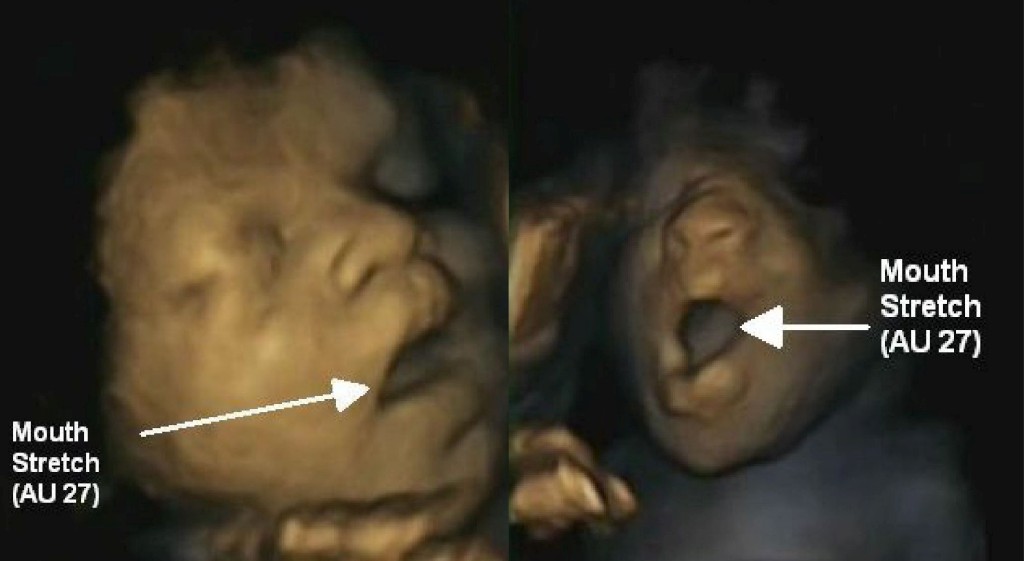

A equipa liderada por Nadja Reissland, do Departamento de Psicologia da Universidade de Durham, estudou 15 fetos – oito raparigas e sete rapazes –, com idades de gestação entre as 24 e as 36 semanas. No total, fizeram 58 ecografias, que permitiam obter gravações em vídeo dos fetos, os cientistas puderam distinguir entre um bocejo (56) e a mera abertura da boca (27) e confirmaram a existência deste movimento nas nossas vidas desde tão cedo.

No bocejo, considera-se que a boca se mantém aberta mais tempo no início do que na parte final. Além desta perspectiva dinâmica do bocejo, difícil de captar noutras ecografias bidimensionais, a sua definição ainda inclui a abertura dos maxilares, uma inspiração profunda, seguida de uma curta expiração, antes de a boca se fechar.